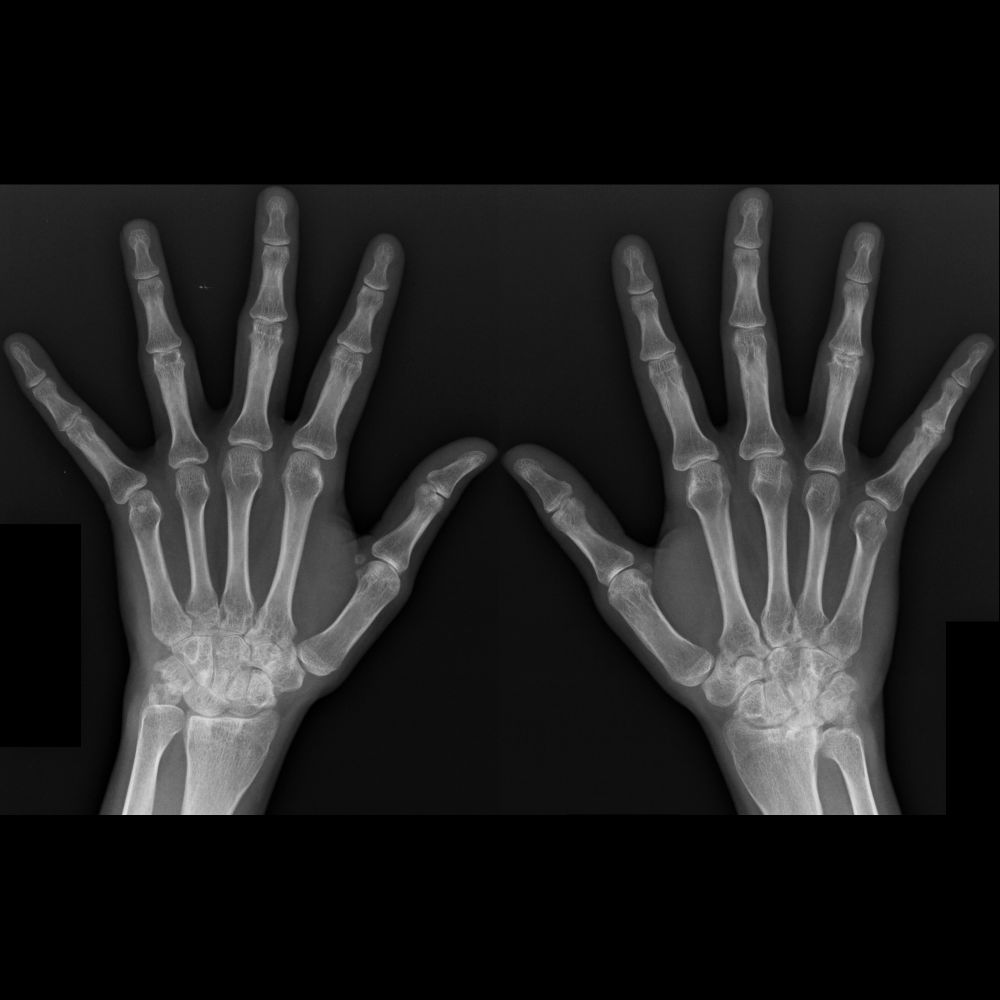

Radiographs of hands shows bilateral periarticular osteoporosis throughout hands. There is bilateral loss of joint spaces in carpal bones due to cartilage destruction+erosions at proximal interphalangeal joints